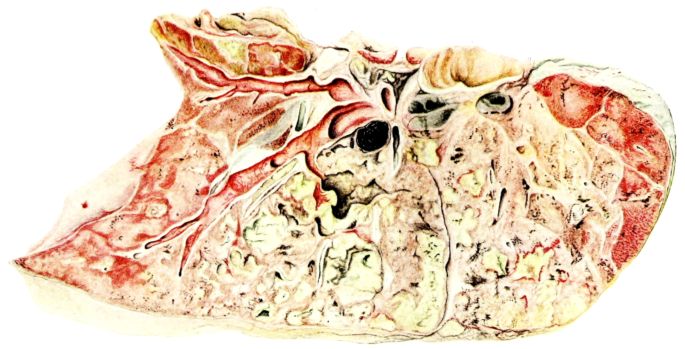

FIG. II. AUTOPSY NO. 98. DRAWING OF A SECTION THROUGH A TRACHEA SHOWING NECROTIZING HEMORRHAGIC INFLAMMATORY PROCESS OF THE MUCOSA.

The changes are less marked, perhaps, in the trachea than in its finer ramifications. The mucosa is constantly more or less destroyed and large areas, usually focal, are entirely devoid of their epithelial covering. This is replaced by a sparse exudate, composed largely of red blood cells, mucus, a small amount of fibrin, and nuclear fragments (Fig. II). It may dip into the submucosa for a short distance, but usually these indentures are associated with the ducts of the mucous glands into which the inflammatory reaction extends. A more striking feature than the exudate, however, is the edema and the congestion of the submucosa. The loose areolar tissue of the submucosa is spread widely apart, and throughout it distended blood vessels are very conspicuous. Occasionally such a vessel is broken and actual hemorrhage appears in the submucosa. Occasionally, too, the inflammation extends down the duct to the mucous gland itself, and here, also, aplastic inflammatory reaction is evident, inasmuch as the acini now stain intensely red with the cells undifferentiated from each other and specked here and there by broken remains of the dead nuclei (Fig. III). After the disease has continued for a short period, even at the end of five or six days, some regeneration of the epithelial lining may be seen (3) (Fig. IV). But despite this, the acute picture persists, and there goes on, side by side, an attempted repair characterized by epithelial regeneration and the same evidence of acute change. Since the lesion is essentially a superficial one, scars or contractures of any extent are not encountered in the trachea, even in examples of the disease that have ended fatally only after many weeks.[4]

19The lungs are extremely voluminous (12, 17) due in part to an accumulation of liquid within them. This finds its way into the trachea and completely fills the latter structure with blood-stained, syrupy fluid, with purulent material, or with a mixture of these (2, 90, 107, 157, 162). At first the pleural surface is smooth and often quite even, but on closer inspection, a minute granulation is suggested. In many cases even close examination does not allow the conclusion that an exudation of anything but serum has occurred through this membrane, except in localized foci. These foci more frequently involve the interlobar pleura and that of the lower lobes (112, 143). The volume of the lungs, often great enough to obliterate the pericardial area, is one of the two most characteristic features of the external examination. The other feature is their color. Small, bright red hemorrhages may occur anywhere. The larger patches are the most striking. Violet, purple, or dark brown areas, irregular in shape and distribution, are more frequently found on that portion of the pleura over the lower two-thirds of the lung. Between the deeply colored zones, there are pale pink areas which involve the lowermost edge to the least degree, the anterior margin somewhat more, and the apex of the lung most of all. The darker portions just referred to may project above the surface and may be circumscribed, resembling huge, fresh hemorrhagic infarcts (41, 108). The alveolar walls are not seen through the pleural surfaces in these darker zones. The pale pink areas, usually at the level of the more intensely colored zones, may be elevated and the dilated air sacs are distinctly made out through the pleura (Fig. XIII). At the hilum, the lymph glands are large and soft. When cut, fluid escapes and is often blood-stained. The cross section may present a distinct, diffuse, hemorrhagic appearance (162). At the hilus, too, the lymphatics, distended here and there over the surface of the pleura, are most affected. The congested bronchial mucous membrane and the exudate in these structures has been described.

After removal, the lung retains its shape, but is more flaccid than the consolidated lung of lobar pneumonia. It cuts with very little resistance and immediately a large amount of a syrupy, pink fluid escapes and obscures the entire area. With the fluid scraped away, the variations in the consistency of the lung become visible. The pale areas around the borders and chiefly at the apex in which the air sacs are discernible with the naked eye, sink slightly below the remainder of the surface, and the pleural edge inverts. The individual lobules of the lung in these areas are more conspicuous than normal, because the interstitial tissue bearing the lymphatics and vessels, as well as that around the bronchi and larger blood vessels, does not lose its edematous appearance as quickly as the alveoli (40, 92, 110, 164), and, consequently, these grey lines and points stand up somewhat more prominently.[6] In contrast with the paler areas which are prone to slight collapse, the remainder of the cross section retains its more smooth and even surface. The alveolar walls are not distinctly made out, but the terminal bronchioles often make themselves evident by the nature of the material which is within and by their distinct dilatation (1, 67, 110, 149, 162). The more firm areas stand out, too, on account of their difference in color. The scheme is not unlike that seen on the pleural surface, and while dark, almost black, infarct-like areas occur on the cut surface, the solid areas are more likely to be translucent, dull, light red, brown or even grey. They have a surface similar to a very fresh, tuberculous, gelatinous pneumonia, but the color differs from the cloudy grey of the latter on account of the admixture of blood in the exudate and the great congestion of the vessels (Fig. XIV).

The well developed post-mortem muscular rigidity, the lividity of the dependent parts, of the face with its mucous membranes, and often of the trunk, the jaundice variable in extent, the crusts of blood on the nares and mouth, and the splanchnic dilatation are features which prepare for the gross picture presented by the thoracic organs. The increased moisture within the pleural cavities associated with the even, translucent pleural surface, whose dilated lymphatics become more and more prominent towards the hilum, the large succulent lymph glands, and the exudate in the bronchial tree, are all striking, but more characteristic of the gross picture, is the great increase in volume of the lung itself, mottled 20with brilliant colors. The lung, too, is very wet and on section, after the syrupy, blood-stained fluid escapes from the less definitely consolidated zones, the latter appear, not as the usual granular, firm areas of hepatization, but have more the consistency of a gel, and also its translucence. Characteristic of this disease as these changes may be, the specificity of the fundamental lesion in the respiratory tract, becomes more emphatic after study of its histology (92, 162).